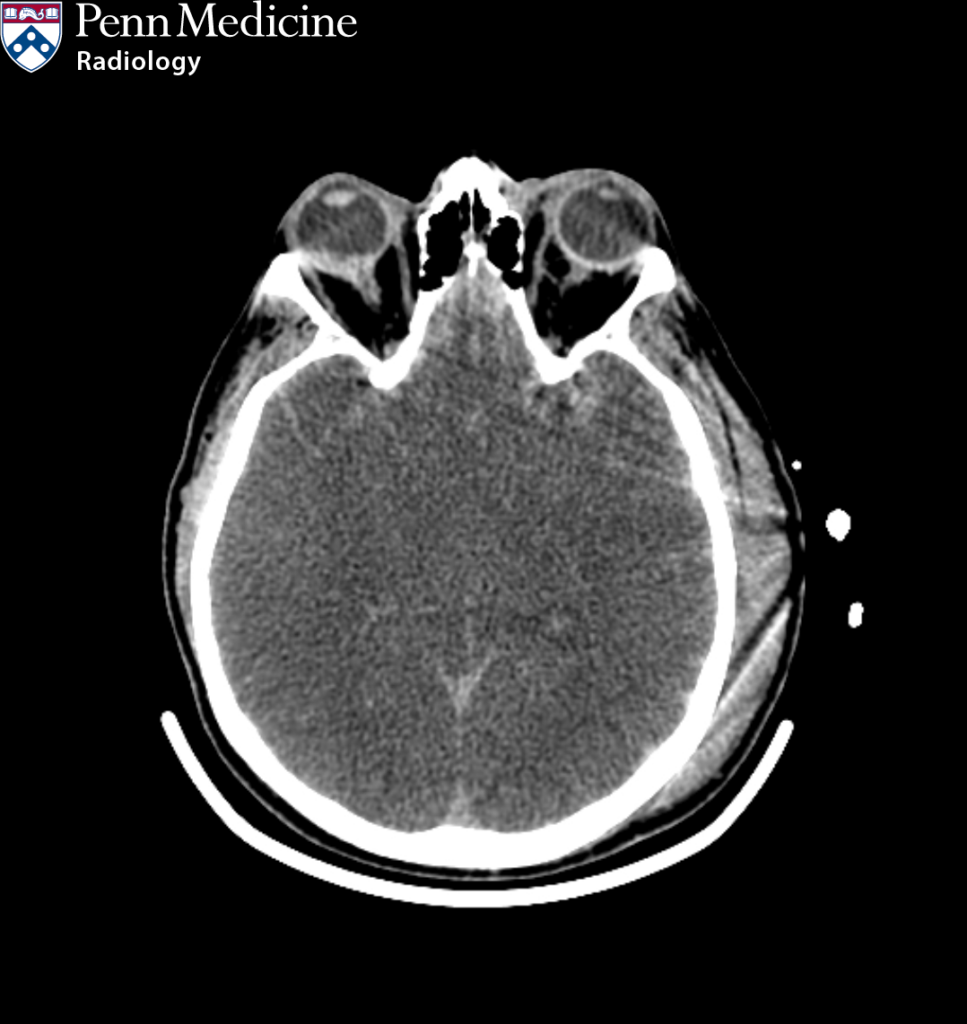

46-year-old man found down

A 46-year-old man found down at home.